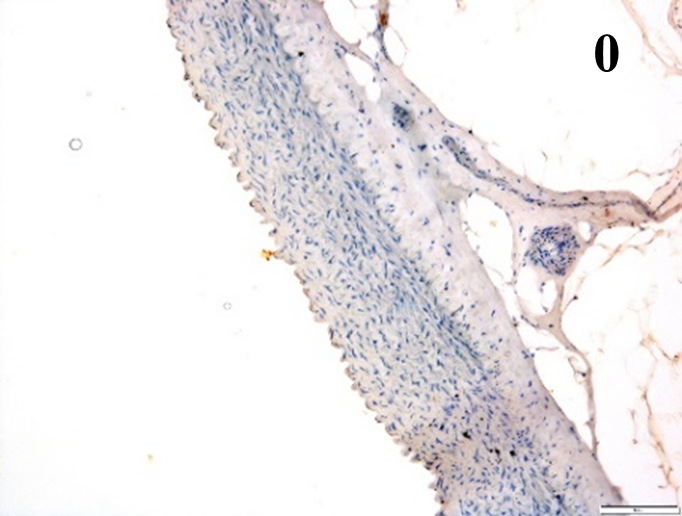

According to the percentage endothelial staining of cells, semi-quantitative

scores were applied. Score: 0 (negative); 1+ (1–10% positive cells); 2+

(11–25% positive cells) and 3+ (